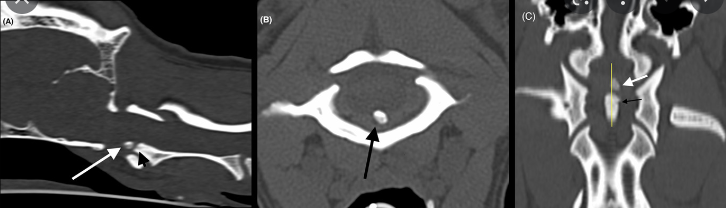

persistent ossiculum terminale가 잔존한 반려견의 CT 자료

CT나 MRI 촬영을 했을때 축추의 치돌기 종말부에 골편이 관찰되는 경우가 종종있는데

이게 AAI 가 치돌기의 골절때문에 일어난것인가? 라고 하기에는 관련 임상증상이 없는 환자가 종종 보인다.

이에 대한 해석에 해당하는 예시라고 생각할 수 있다.

즉, dens fracture일 수도 있지만 POT일 수 있다는 의미 이다.